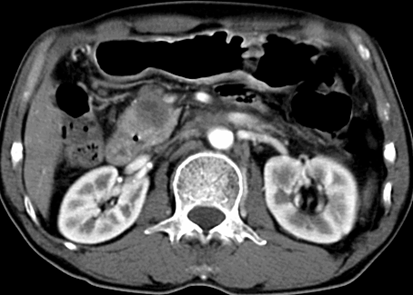

주로 돌이나 종양 때문에 담관이 막혀 염증이 발생하는데 담관염이 확인되면 먼저 응급으로 내시경을 이용하여 (ERCP) 쓸개즙을 배농시켜야하며 때에 따라서 막힌 부위를 뚫어 주어야합니다.

이러한 시술이 여의치 않으면 해상력이 좋은 초음파를 이용하여, 피부를 통하여 직접 담관에 관을 삽입해 쓸개즙과 염증을 배농시켜주어야 합니다.